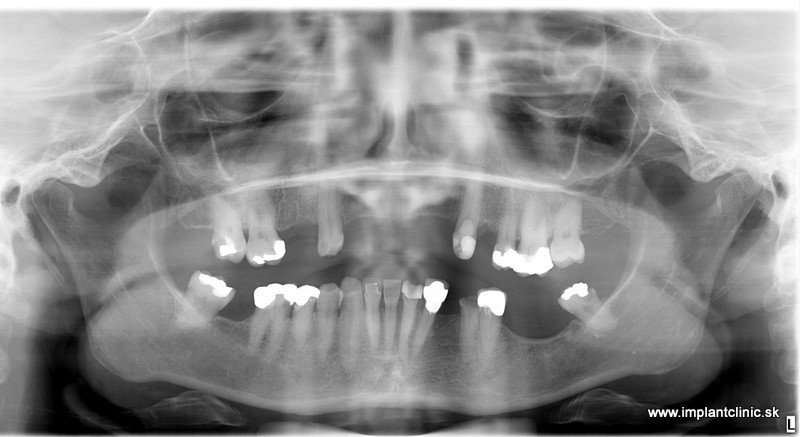

Snímok chrupu pred ošetrením

Zanedbávanie pravidelných prehliadok a zlá orálna hygiena je najčastejším dôvodom ochorení parodontu. Ak tieto ochorenia neliečime a ignorujeme, dôsledky môžu byť vážne. Najčastejším signálom zápalu je krvácanie pri podráždení a začervenanie ďasna. Takéto prejavy signalizujú, že niečo nie je v poriadku. Treba navštíviť lekára ktorý odhalí príčinu krvácania. Ďalším dôvodom prečo naši pacienti prichádzajú o zuby je strach z ošetrenia.

Rekonštrukciu chrupu v celkovej narkóze podstúpila aj naša pacientka Jana. Objednala sa na bezplatnú konzultáciu v Implantclinic. MUDr. Salka navrhol pacientke následovný plán ošetrenia.

Vrchná čeľusť : 5 extrakcií, 6 zubných implantátov, 12 – členný keramický mostík

Spodná čeľusť: 11 extrakcií 6 zubných implantátov 12 – členný keramický mostík